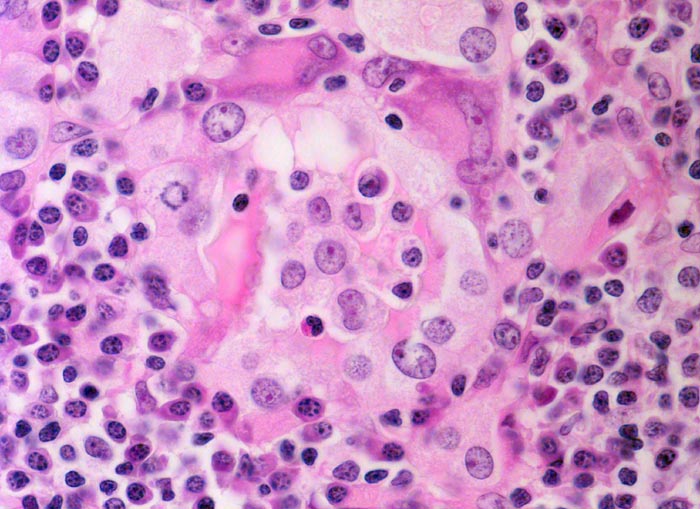

chronische lymphozytäre Thyreoiditis Hashimoto

Ein dichtes Lymphoplasmazelluläres Entzündungsinfiltrat zerstört das Follikelepithel (helle Zellen mit viel Zytoplasma und grossen Kernen). Vereinzelt sind auch Riesenzellen erkennbar. Die zerstörten Follikel enthalten nur noch wenig Kolloid.